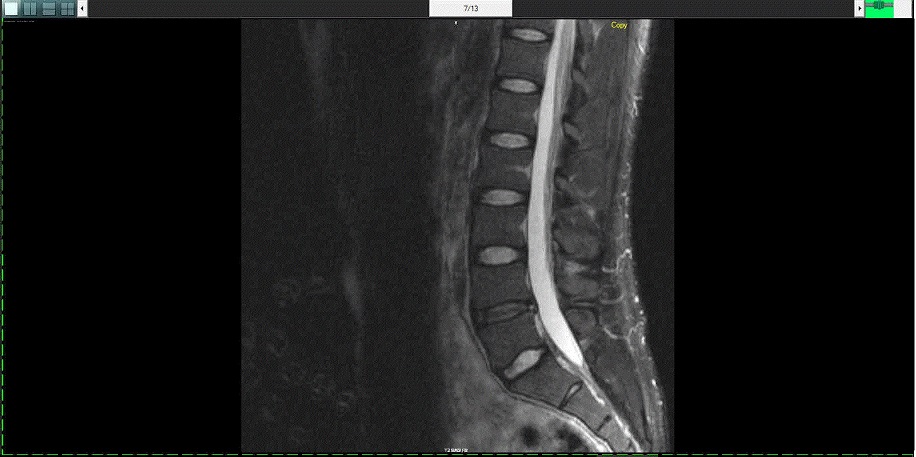

也可能是个“医疗影像”